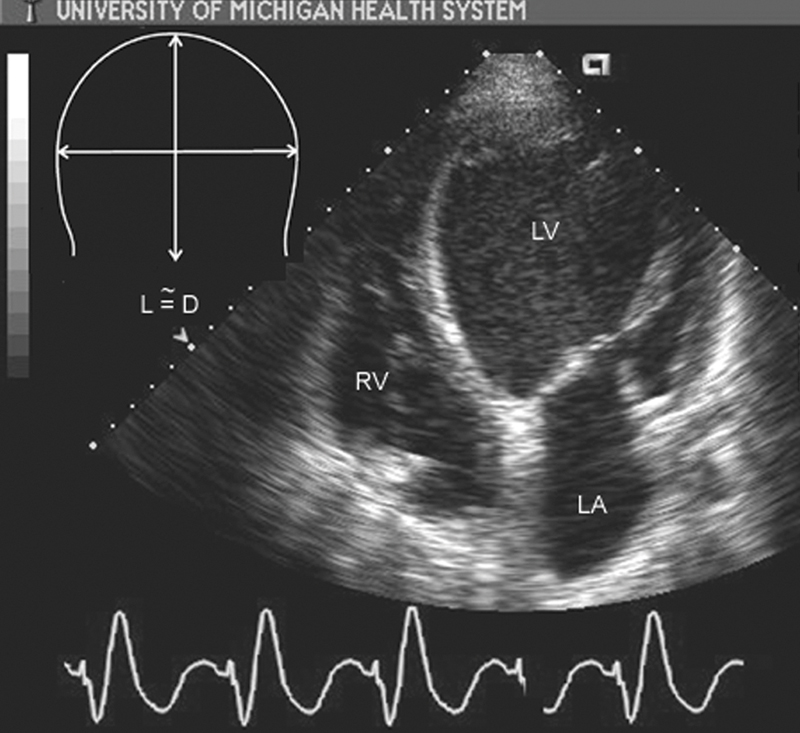

فحوصات تشخيصية لبعض امراض القلب والشرايين التاجية